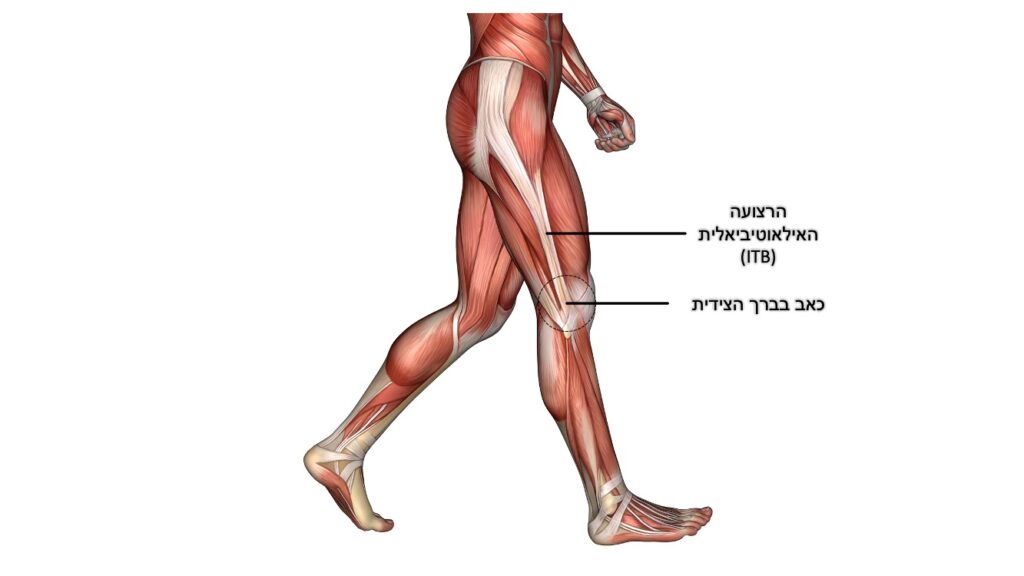

תסמונת המאמץ של עצם השוק הפנימית

Medial Tibial Stress Syndrome

או בשמה ההיסטורי – שין ספלינט (Shin splint). תופיע ככאב בשוק המרוחקת (מעל הקרסול), לרוב בחלק הפנימי של השוק. הכאב מתחיל ככאב מקומי עמום תלוי פעילות. לרוב יתארו הרצים/רצות כאב שהתחיל בתחילת הריצה וחלף בהמשכה. עם ההחמרה בסימפטומים, הכאב לא יחלוף במהלך הריצה ואף ימשך לאחריה. ברוב המקרים ניתן לעורר כאב במישוש עמוק באזור, גם בזמן מנוחה. עיקר הרגישות על הגבול הפנימי/אחורי של עצם השוק המרוחקת.

הדעה המקובלת היא שמדובר על עומס חוזר הגורם לתהליך שחיקתי/דלקתי המערב את העצם, מעטפת העצם והגידים של השרירים המתחברים באזור זה לעצם (Soleus, Flexor digitorum longus).

פציעה זו שכיחה יותר בנשים, רצים/ות עם יחס משקל/גובה גבוה (BMI גבוה), כיפוף כפי (Plantar flexion) מוגבר במפרק הקרסול, סיבוב חיצוני מוגבר במפרק הירך ובעיות מבניות בכף הרגל (קשת נמוכה והיפר פרונציה). קיים מידע מוגבל גם על קשר בין חוסר ויטמין D ושכיחות מוגברת של פציעה זו. חשוב להדגיש שגורמי הסיכון המופיעים מעלה אינם בהכרח יביאו לפציעה, אלא בשילוב עם תוכנית אימונים לא מתאימה וגורמים נוספים שהוזכרו כתורמים לפציעות "שימוש יתר".

במסגרת תהליך האבחון יש לשלול סיבות אחרות לכאבים דומים כגון: תסמונת מדור הקשורה במאמץ, שבר מאמץ ועוד. על כן, חשוב לעבור הערכה רפואית מקצועית של מומחה בתחום.

הטיפולים מבוססים על שינוי דפוס פעילות תוך הימנעות זמנית מהפעילות הפרובוקטיבית (ריצה), טיפול בבעיות מבניות (לדוגמא: מדרסים), תרגול וחיזוק של שרירי כף הרגל, הקרסול והשוק, שיפור טכניקת ריצה, העמסה הדרגתית וחזרה לפעילות. כמו כן, ניתן לשקול טיפול בגלי הלם (extracorporeal shockwave therapy).

טיפולים מקובלים עם רמת הוכחה נמוכה יותר כוללים טיפול מקומי באולטרסאונד או חשמל, עיסוי מקומי ונטילת ויטמין D במקרים של חוסר. אין הוכחה שסדים מסוגים שונים או גרבי לחץ (Compression) הם טיפולים יעילים.